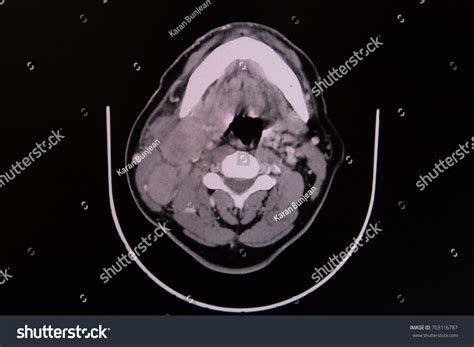

A CT scan of neck, often referred to as computed tomography, is a sophisticated diagnostic imaging procedure that utilizes X-rays combined with computer processing to create detailed, cross-sectional images of the structures within your neck. Whether your physician is investigating a persistent lump, evaluating unexplained pain, or monitoring a known condition, this imaging tool provides a level of clarity that standard X-rays cannot match. By capturing slices of the neck’s anatomy—including the thyroid gland, lymph nodes, blood vessels, and spinal structures—doctors can pinpoint abnormalities with remarkable precision, making it an essential component in modern diagnostic medicine.

The technology behind a CT scan of neck is fascinating. The patient lies on a motorized table that slides into a large, doughnut-shaped scanner. As you move through the scanner, an X-ray tube rotates around you, sending thin beams of radiation through your body. Detectors on the opposite side of the scanner record these beams, and the computer processes this information to create detailed, 3D-like images of the internal structures.

In many cases, the radiologist may decide that a contrast dye is necessary to enhance the visibility of specific tissues, blood vessels, or abnormalities. This contrast material, usually iodine-based, is typically injected into an intravenous (IV) line in your arm before the scan begins.